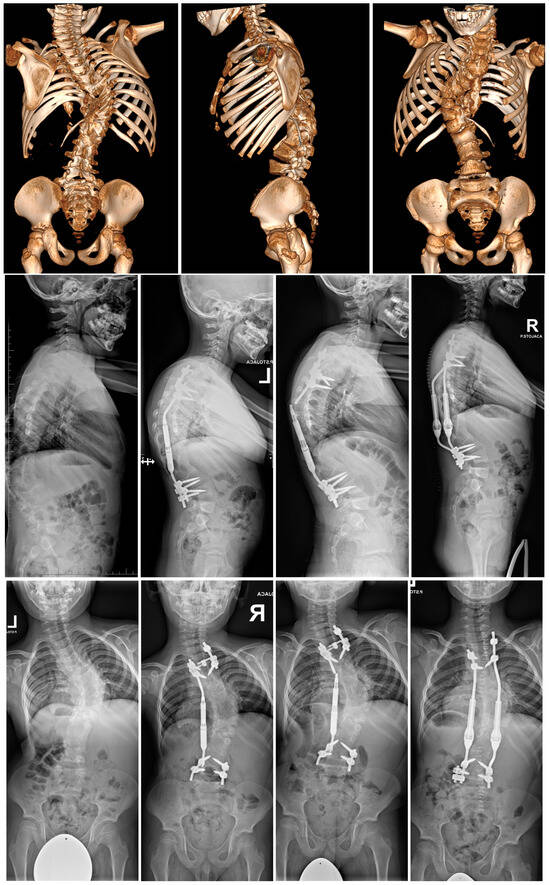

- Grabala, P.; Gupta, M.C.; Pereira, D.E.; Latalski, M.; Danielewicz, A.; Glowka, P.; Grabala, M. Radiological Outcomes of Magnetically Controlled Growing Rods for the Treatment of Children with Various Etiologies of Early-Onset Scoliosis—A Multicenter Study. J. Clin. Med. 2024, 13, 1529. [Google Scholar] [CrossRef] [PubMed]